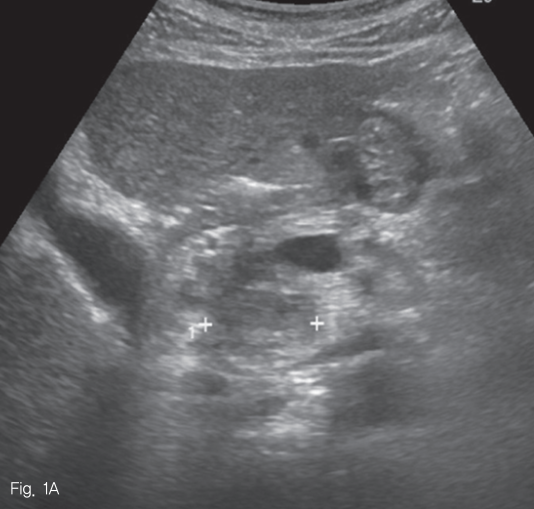

초음파 검사에서 췌장 두부에 약 2.5cm 크기의 종괴가 있었다 (Fig. 1). 췌장 자기공명영상에서 종괴는 T1-weighted image에서 다양한 신호강도를 보였고, T2-weighted image 에서는 저신호강도를 보여 다양한 단계의 출혈을 포함한 병변으로 생각하였다 (Fig. 2A-B). 조영 증강 자기공명영상 및 조영 증강 복부 전산화단층촬영에서 종괴의 내측으로 혈관과 비슷한 조영 증강을 보이는 1cm 크기의 병변이 보여 가성동맥류로 진단하였다 (Fig. 2C-D).

Fig 1

Abdominal sonogram reveals a 2.5cm-sized mass in pancreatic head (cross signs).